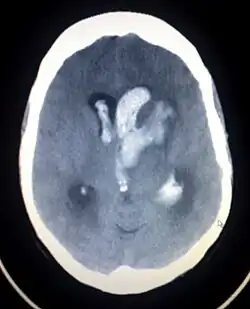

| Axiali CT scan of a spontaneous intracranial hemorrhage | |

A non-contrast CT scan (computed tomography) of the brain is commonly used as the initial imaging modality in suspected cases of intracranial hemorrhage. CT is preferred in emergency settings due to its speed, availability, and high sensitivity for detecting acute brain injuries, enabling rapid triage and surgical decision-making. Examples of brain diseases that require urgent intervention are: large-volume hemorrhage, brain herniation, and cerebral infarction. Additional advantages of CT imaging include its effectiveness in detecting bony fractures, vascular injuries, and cerebrospinal fluid (CSF) leaks.

A swirl sign on CT imaging— representing areas of low density with surrounding areas of high density— suggest active intracranial bleeding. The presence of this sign is associated with an increase in risk of death within one month and a poor functional prognosis at three months among survivors.[6]